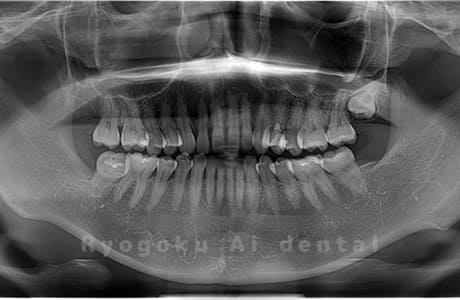

Case02

- 原因

- 下顎の水平埋伏智歯

- 治療内容

- 下顎の水平埋伏智歯を抜歯

<リスク・副作用>

手術後は痛み、腫れ、痺れなどの副作用が生じる場合があります。